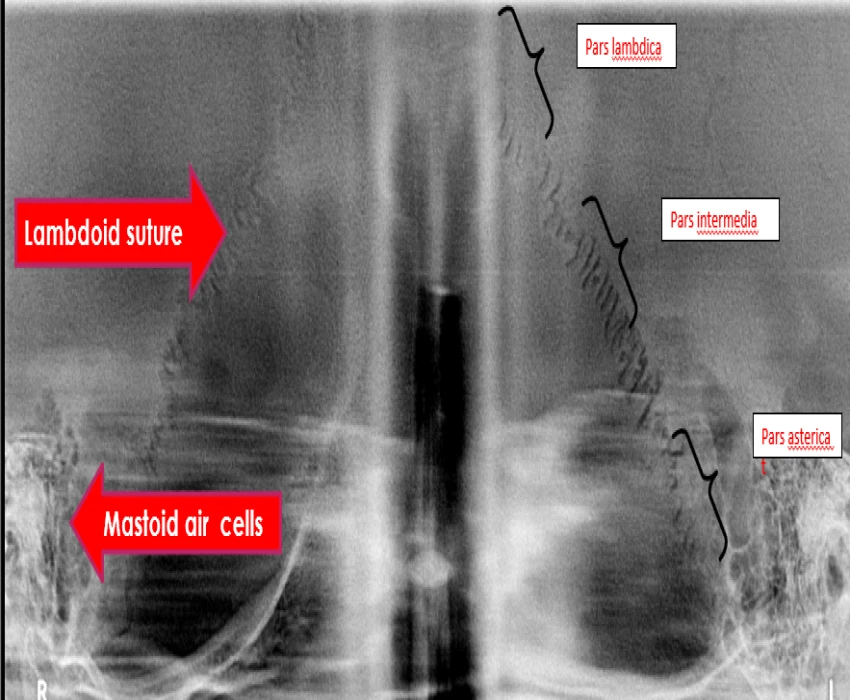

Reverse panoramic Radiography is a useful and promising technique for the initial preliminary imaging of the various anatomic structures like temporomandibular joint and its associated structures, mastoid air cell, lambdoid suture and occipital region and can be further explored in the near future.